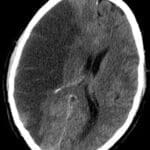

ICH

Admission Template